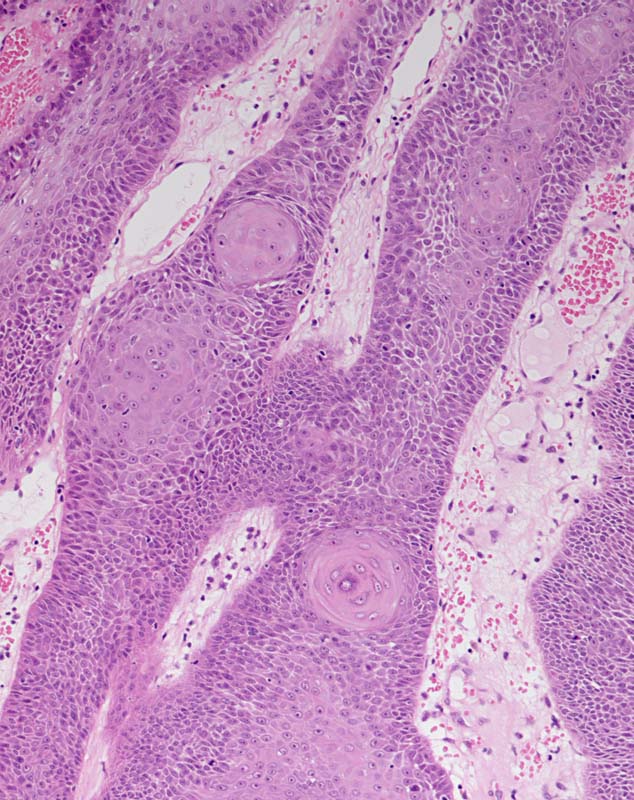

PathoPic ID 8065 - Irritierte seborrhoische Keratose

Irritierte seborrhoische Keratose

benigner Tumor

Haut, Rumpf

Haut

Basaloide Zellstränge mit mehreren

Squamous Eddies und umgeben von ödematöser Dermis.

Traumatisiertes Fibroma pendulans am Rücken.

Histologie

100